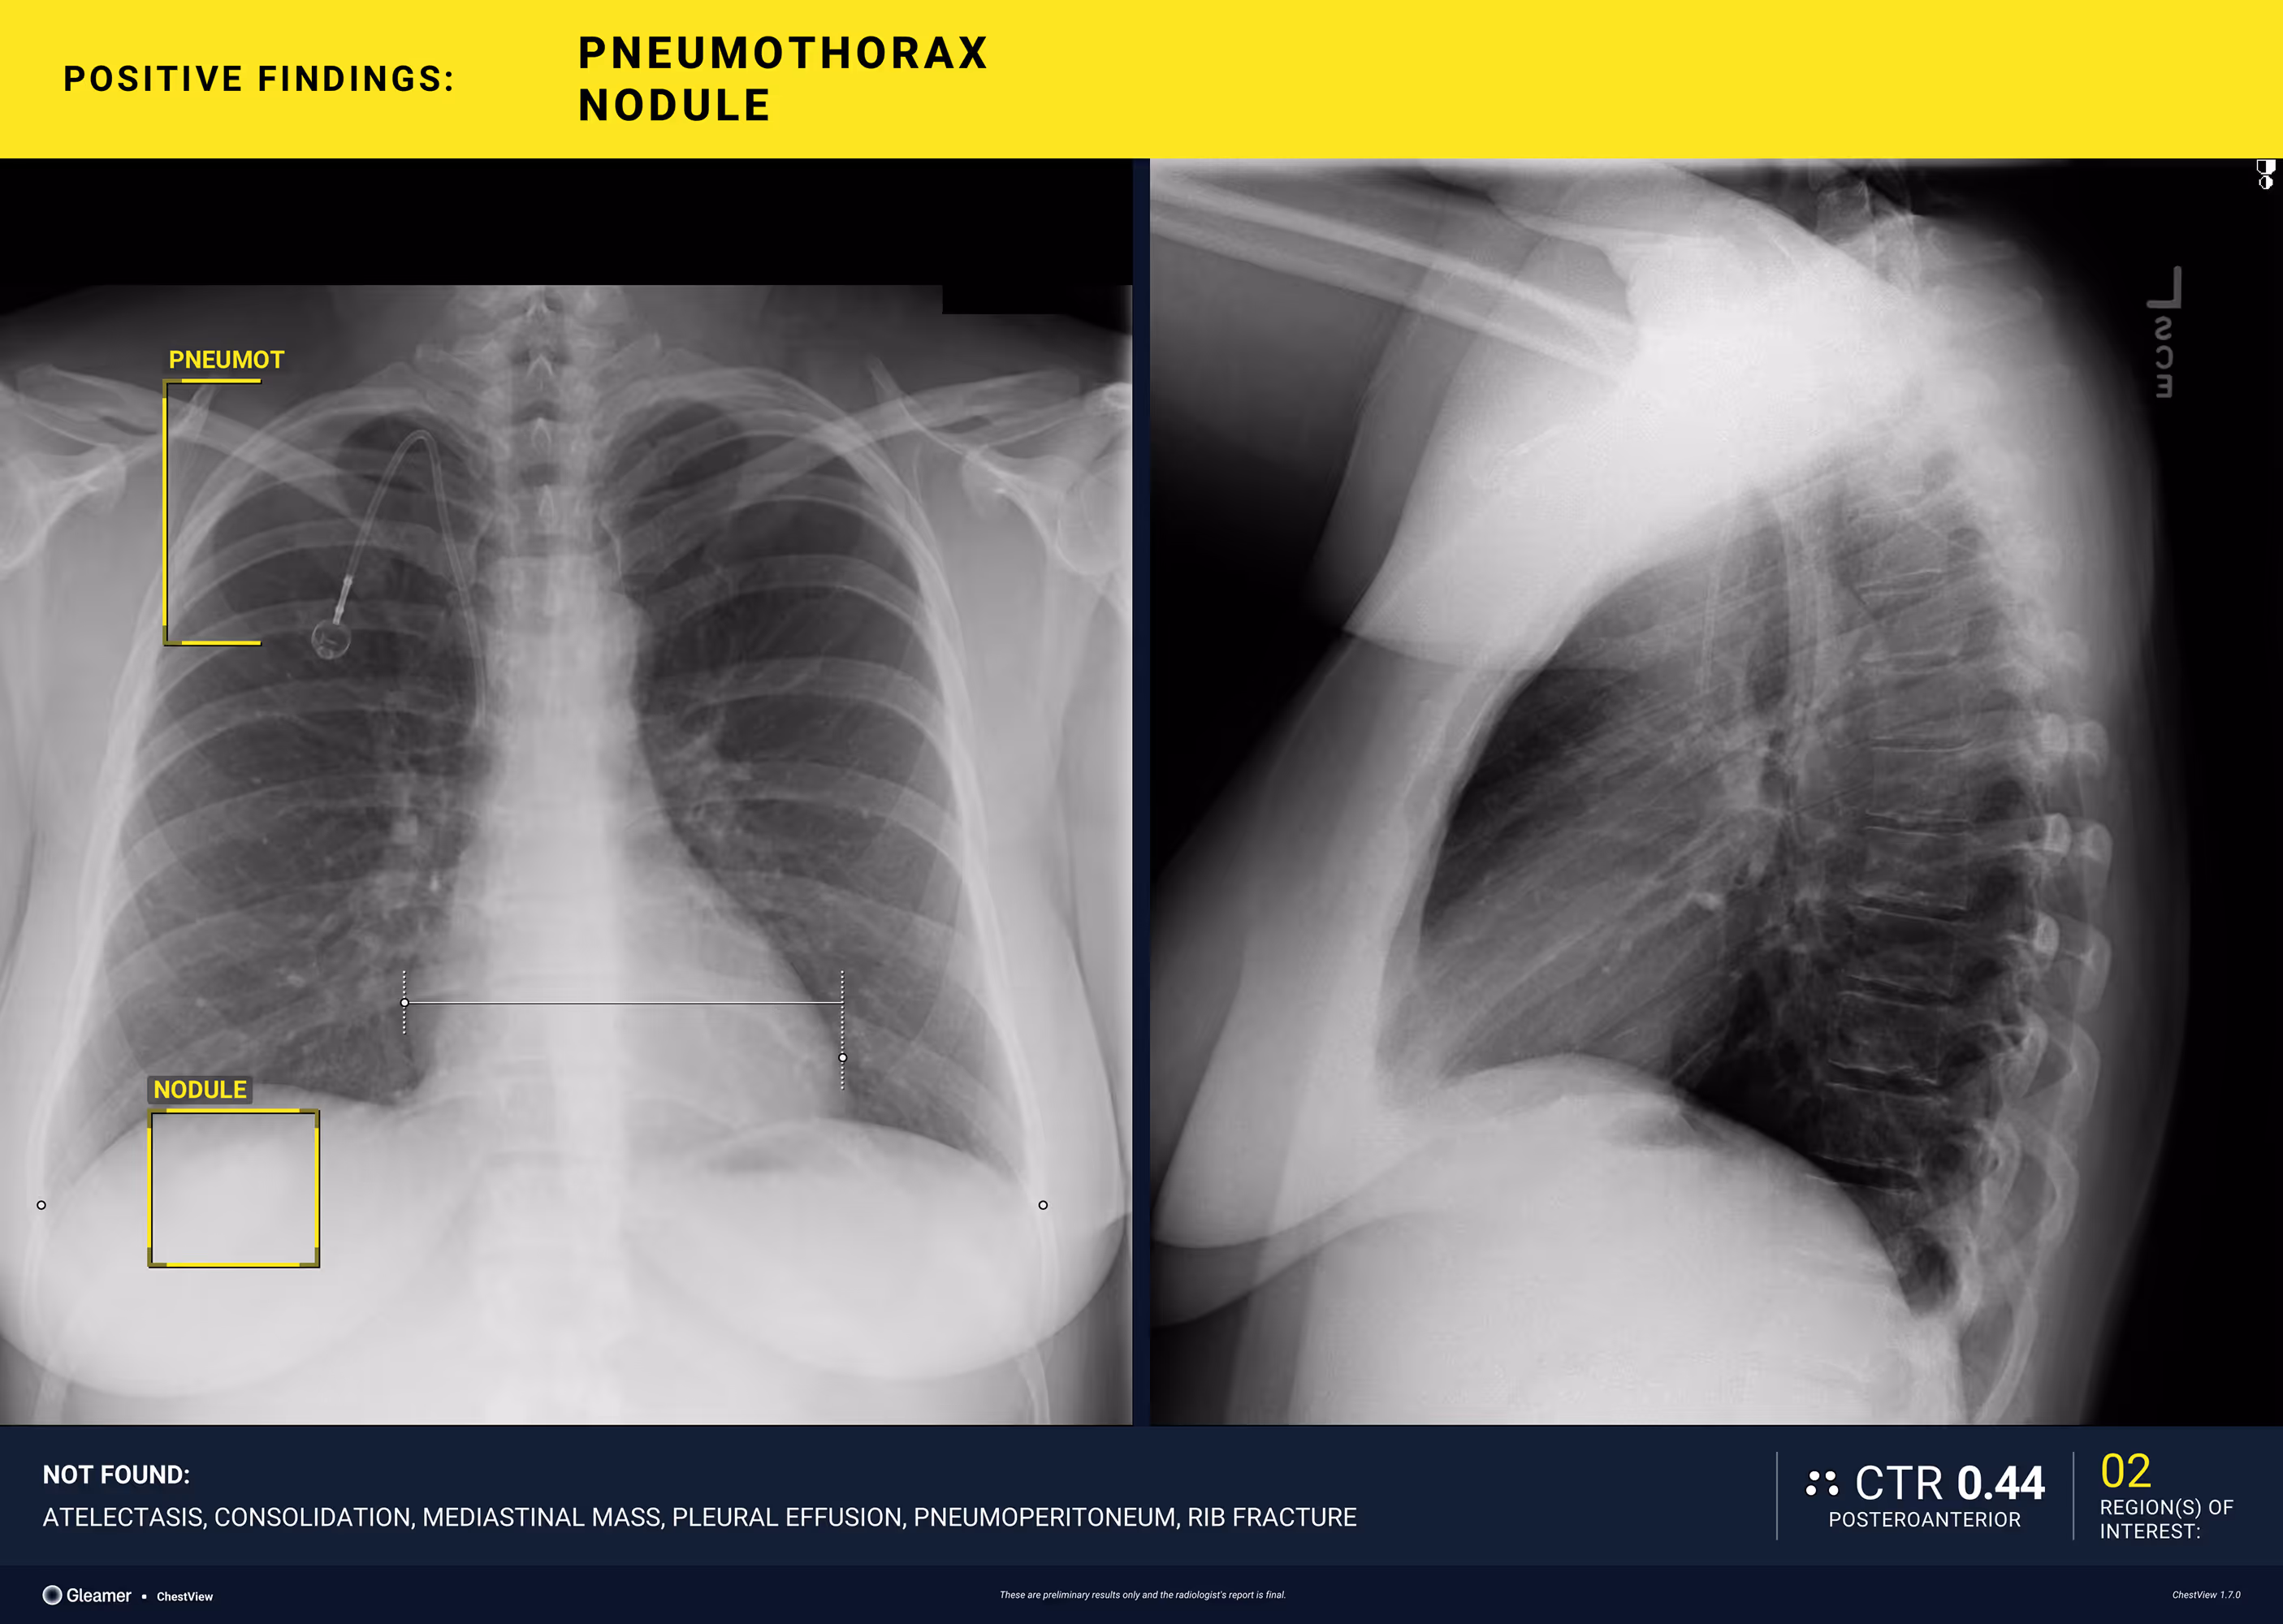

A 40-year-old female with a history of colon cancer presents for a control radiograph following biopsy of a right lower-lobe pulmonary nodule.

Results

ChestView detected a pneumothorax post-biopsy.